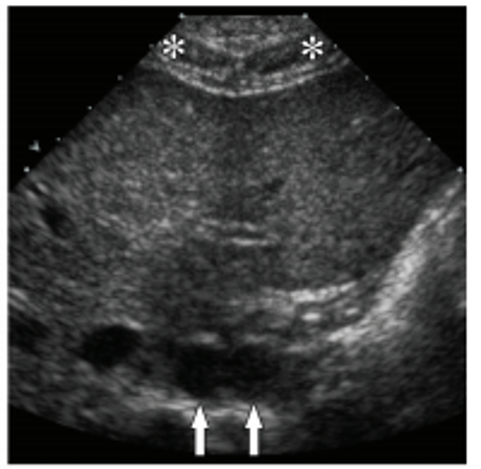

mirror image artifact.

the diaphragm almost ALWAYS causes mirror image artifact due to the difference in acoustic impedance between air and liver.

*If NO mirror image artifact is seen in the lung base —> PLEURAL EFFUSION